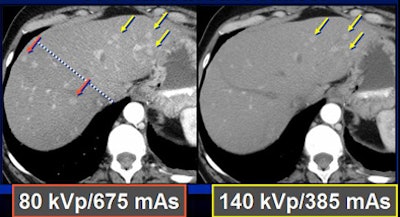

Because low kVp is closer to the K-edge of iodine, the attenuation of iodine structures increases as kVp decreases. Thus, a CT image of an iodine structure imaged at 140 kVp is about 200; dropping the kVp to 80 nearly doubles the attenuation, even though tube energy is reduced, Nelson explained.

In a phantom model tested by the Duke team, iodine structures were seen more clearly when attenuation was reduced. Similar results were found in patients with hepatic lesions; some subtly hyperenhancing liver lesions could be seen only at lower kVp levels.

To test the hypothesis quantitatively, Duke researchers performed a study of 48 patients with 68 hyperenhancing live lesions, scanned using a dual-energy volume technique (GE Healthcare, Chalfont St. Giles, U.K.) during the arterial phase, Nelson said. One rotation was scanned at 80 kVp and 540 mAs; a second was acquired at 140 kVp and 308 mAs. The results showed significant differences in lesion conspicuity with the use of low-kVp imaging.